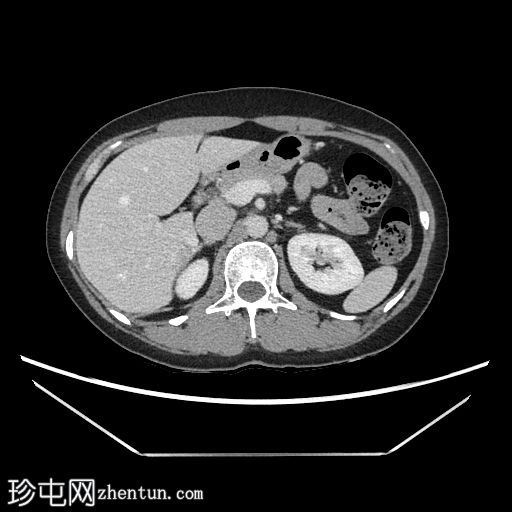

CT扫描

轴向

非造影

在轴向、冠状面和矢状面上均可见肝5/6段病变。动脉期可见周围结节状强化,门静脉期可见进行性向心性充盈,延迟期亦持续存在。这些表现为肝血管瘤的特征性表现。